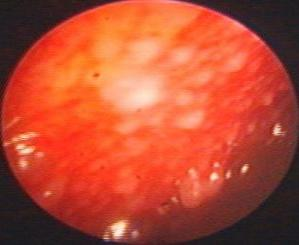

近年来,贵州航天医院各科室紧跟医学前沿,不断强技术、补短板,大力开展新技术、新项目,完成了许多高精尖、高难度、本地区“首例”的技术,填补了医院医疗技术空白,满足了群众日益增长的医疗需求。 贵州航天医院呼吸与危重症医学科是贵州省内呼吸疾病治疗规模最大,诊疗项目最全的呼吸疾病品牌科室,呼吸介入技术达到了全国先进水平,在贵州省内处于领先的地位。 本期,我们将为大家带来呼吸与危重症医学科特色技术——内科胸腔镜技术诊断和治疗胸腔疾病。 案例分享 患者苟某某,因劳累、气促,不明原因胸腔积液在某县一医院采取反复抽水等治疗手段效果不佳,当地医院考虑到患者年龄大(77岁),基础疾病较多,病情复杂,结合当地诊疗水平能力情况,建议转到上一级医院诊治,通过我院与该院建立的呼吸专科联盟绿色通道转入了我院。 患者入院后,呼吸与危重症医学科第一时间复查胸部CT,提示:右肺中叶、左肺感染,纤维化灶,左侧中量胸腔积液,右后侧胸膜轻度增厚,心包少量积液;并完善心电图、血常规、凝血功能、生化指标等术前检查。经科室专家团队集体讨论,得出患者左侧胸腔积液可能原因:结核?恶性?其他?冠心病、心功能不全、高血压病3级(高危组)、陈旧性肺结核复发?肺部感染;为进一步明确诊断,在充分评估、做好术前准备及应急预案、与患者及家属沟通的情况下,决定为患者进行内科胸腔镜检查术。 科室在患者入院第3天便实施了内科胸腔镜检查术,经检查取活检,病理不排除胸膜间皮瘤,送遵义医科大学附属医院病理会诊后诊断:胸膜间皮瘤。明确诊断后,科室专家团队为患者制定了个体化的治疗方案,患者病情很快得到有效控制,最终满意出院。半年后,医院通过电话回访,患者病情稳定,生活质量明显改善。 什么是内科胸腔镜 内科胸腔镜(medical thoracoscopy,MT)是一项微创诊断和治疗胸腔疾病的重要技术。主要应用于无创方法不能确诊的胸腔积液和胸膜疾病,通过局部麻醉后在胸壁做一个小切口,插入胸腔镜,直接观察胸膜、肺表面、纵隔等部位的病变情况,可进行活检、粘连松解及胸膜固定等操作。具有创伤小、恢复快、诊断准确性高等优点。 内科胸腔镜原理 内科胸腔镜是一项利用现代光学技术和成像技术的侵入性操作技术,应用电子支气管镜、硬质或软硬结合(半硬)的胸腔镜的一种电子内窥镜,末端装有连接着显示屏的微型摄像头。通过胸壁1-2cm左右的小切口,将内科胸腔镜及专用器械(戳卡套管)通过小切口进入胸腔,微型摄像头将胸腔内的情况投射到显示屏幕上,医生可以通过镜头全面、直观地观察患者胸腔内情况,了解胸膜病变确切位置和形态改变,还可对胸膜上的病变进行活检及治疗的操作技术,安全、微创、几乎无痛地“揭秘”不明原因的胸腔积液。 内科胸腔镜技术优势 (一)安全性高:仅需局部浸润麻醉,并发症发生率相对较低,对患者的身体条件要求较低。 (二)操作简便:操作时间短,痛苦少,患者耐受好。 (三)微创性:切口小,对患者身体损伤小,术后疼痛轻,恢复快。 (四)高分辨率成像:清晰显示胸腔内细微病变,提高诊断准确性。 (五)可直视操作:直接观察病变,进行精准活检和治疗。 (六)适用范围广:可用于不明原因胸腔积液、胸膜疾病、肺部疾病等的诊断和治疗。 (七)费用低:与外科胸腔镜比较费用低廉。 内科胸腔镜技术是贵州航天医院呼吸专科和呼吸介入诊疗优势的一部分,在2016年率先开展了内科胸腔镜技术,年手术量约100余例,已建立了快速、精准、规范、有效的一体化诊疗服务体系。目前呼吸与危重症医学科内科胸腔镜技术广泛应用于不明原因胸腔积液、气胸、脓胸的诊断和肺癌、弥漫性恶性胸膜间皮瘤等的分期,恶性或复发性胸腔积液、早期脓胸、自发性顽固性气胸的治疗。 镜下常见表现:单发或多发结节、灰白色弥漫性粟粒样结节、胸膜充血、水肿、胸膜增厚及纤维分隔或粘连带形成。 诊断方面: 胸腔积液的病因诊断。内科胸腔镜对恶性胸腔积液的诊断率可高达90%以上,胸腔镜对结核性病变诊断率极高,几乎达到96%以上。 腺 癌 恶性淋巴瘤 软骨肉瘤胸膜转移 滑膜肉瘤胸膜转移 结核性胸膜炎 治疗方面: 脓胸 肺大泡 贵州航天医院 呼吸与危重症医学科学科带头人 廖江荣 国务院政府特殊津贴专家 二级教授 主任医师 贵州航天医院副院长 国家级学术任职: 第二届中国医药教育协会介入微创专业委员会呼吸分会副主任委员 中国抗癌协会肿瘤微创治疗专业委员会常务委员 中国防痨协会结核病转化医学专业分会常务委员 第一届中国人体健康科技促进会呼吸介入专委会常务委员 中国医疗保健国际交流促进会结核病学分会第三届委员会常务委员 中国抗癌协会肿瘤微创治疗专业委员会粒子治疗学组第四届委员会委员 中华医学会结核临床专业委员会内镜介入委员 中华医学会放射学分会第十五届委员会介入学组呼吸系统介入专业委员会委员 北京健康促进会中青年专家委员会胸部疾病精准活检分委会副主任委员 中国医师协会介入医师分会第二届委员会肿瘤消融专业委员会委员 中国结核病防治综合质量控制专家指导委员会委员 亚洲冷冻治疗学会常务委员 世界内镜医师协会呼吸内镜协会常务理事 内镜临床诊疗质量评价专家委员会委员 “西部呼吸介入联盟”副理事长 专业擅长: 贵州航天医院 呼吸与危重症医学科简介 贵州航天医院呼吸与危重症医学科以呼吸危重症和介入呼吸病学为强力推手,以肺部感染性疾病及肺癌、肺小结节的早期精准诊疗、慢性呼吸疾病康复治疗为特色,以人才团队建设为核心的科室发展模式,现已成为省内呼吸疾病治疗规模最大,诊疗项目最全的呼吸疾病品牌科室。是贵州省医学重点学科、临床医学重点专科建设单位,遵义市首批呼吸重点学科、重点专科建设单位。是国家卫健委能力建设和继续教育肿瘤微创介入建设中心、贵州省县级医院微创介入培训中心、遵义市呼吸疾病临床医学中心。是国家呼吸医疗质量控制与管理哨点医院、遵义市呼吸内科专业医疗质量控制中心。是中国医药教育协会介入微创呼吸分会呼吸介入技术培训中心单位;国家卫健委海医会呼吸分会ROSE专委会“诊断性介入肺脏病学快速现场评价”培训基地;中国肺癌防治联盟“贵州航天医院肺结节诊治”分中心,中国人体健康科技促进会呼吸介入技术培训基地,贵州省中西医结合会呼吸学分会呼吸介入专委会主委单位。 基本情况 平均每年开展气管镜诊疗约4000例,经皮肺穿刺介入诊疗近千例,开展的项目包括经支气管镜(软、硬)下冷冻、氩气刀、高频电刀、球囊扩张、支架置入、超声内镜诊疗等气道介入诊疗技术,经皮肺穿刺活检及肿瘤消融术(微波、冷冻)、ROSE技术、内科胸腔镜诊疗及经血管介入诊疗技术,且多项呼吸介入诊疗技术在省内处于领先水平。 诊疗范围 航天医院呼吸专科擅长:致力于呼吸系统感染性、疑难性疾病的介入快速精准诊疗;肺癌与肺小结节早期精准诊疗水平项目提升。擅长于呼吸系统(肺)疑难病的诊断及危重病的救治,尤其在肺癌、肺小结节的早期诊断;肺癌综合靶向治疗;肺结核综合诊疗;肺部疾病的介入诊疗在省内处于前沿水平。 咨询热线 (一)呼吸与危重症医学科一病区 医生办公室:27677317 护士站:28614217 (二)呼吸与危重症医学科二病区 医生办公室:28691274 护士站:28690442 (三)呼吸与危重症医学科三病区 医生办公室:28692417 护士站:28690461 (四)呼吸与危重症医学科四病区 医生办公室:28616402、27677582 护士站:28614987、27677862